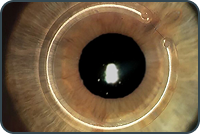

A partir disso, realizamos exames detalhados que permitem avaliar com precisão as diferentes estruturas do olho.

A avaliação oftalmológica muitas vezes exige exames específicos para compreender melhor a estrutura e o funcionamento do olho.

Esses exames ajudam a identificar alterações precoces e permitem um diagnóstico mais preciso.

avaliação da retina, córnea e nervo óptico